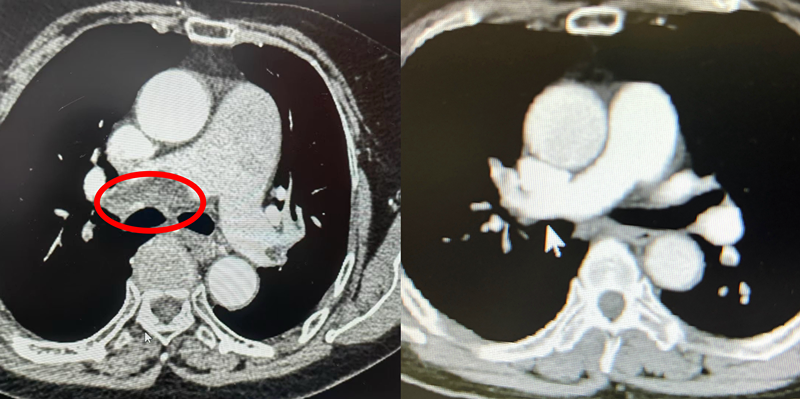

(治疗前后影像对比,肺动脉血栓明显减少)

救护车上是象州县人民医院的急救人员,在对李女士进行积极抢救后立马转运回医院完善了检查,结果提示肺动脉栓塞,连夜送到广西科大一附院胸心血管外科治疗。入院后李女士疼痛不已,呼吸急促、大汗淋漓,血氧饱和度降低,胸心血管外科黄小龙主任评估后立即带领团队为李女士进行急诊下腔静脉滤网置入术+肺动脉吸栓术,历经一个小时手术便圆满成功。术后李女士呼吸、疼痛情况得到明显改善,血氧饱和度也恢复了正常,广西科大一附院凭借急、危、重症应急处理能力,让患者得到了及时有效的救治。